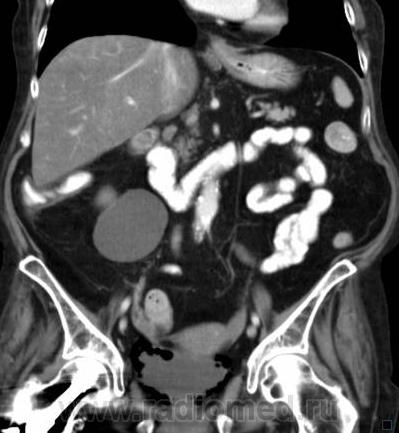

О чём могут говорить такие "газовые структуры" в области мочевого пузыря?

Наличие газа в мочевом пузыре может говорить о многом. Например стоял катетр Фолея, состояние после цистоскопии, эмфизематозный цистит, наличие фистулы.

А, чем именно, будет характеризоваться эмфизематозный цистит? При нем "пузырьки газа" локализуются в слизистой оболочке или где?

В просвете, может быть и в самой стенке. Смотрите здесь:

процесс в стенке в данном случае.

У женщины киста правой почки, подозрение на жировой гепатоз, стержень в головке и шейке правого бедра (остеосинтез). А про воздух возле/в стенке мочевого пузыря... не было ли оперативного вмешательства в малом тазу? И без аксиальных срезов явно я бы не сказала, где конкретно воздухblush...

Фик с ней с кистой... И какая разница аксиалы и короналы... Да, толстоваты срезы, эффект усреднения. Но я бы думал в сторону язвенного/гангренозного цистита (эмфизематозного цистита). Естественно, анамнез и клиника и всё встанет на свои места. На состояние после катерера не очень похоже...